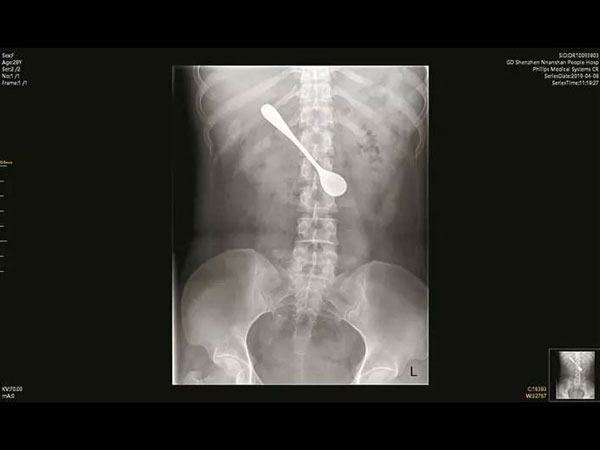

വിഴുങ്ങിയത് 5 ഇഞ്ചിന്റെ സ്പൂണ് പക്ഷേ സംഭവിച്ചത്

ഭക്ഷണം കഴിക്കുമ്പോള് പല വിധത്തിലുള്ള ബുദ്ധിമുട്ടുകള് പലരിലും സംഭവിക്കാറുണ്ട്. എന്നാല് പലപ്പോഴും ഭക്ഷണം തൊണ്ടയില് കുടുങ്ങുമ്പോള് അത് പരിഹരിക്കാന് നെട്ടോട്ടമോടുന്നവരും ചില്ലറയല്ല. എന്നാല് ഇത് അല്പം കൂടി കടന്ന് പോയി എന്നാണ് നിങ്ങള്ക്ക് ഈ ലേഖനം വായിക്കുമ്പോള് തോന്നുക. കാരണം അഞ്ച് ഇഞ്ചിന്റെ സ്പൂണ് ആണ് ഇവര് വിഴുങ്ങിയത് എന്നതാണ് സത്യം. പക്ഷേ സാധാരണയായി നമ്മുടെ തൊണ്ടയില് എന്തെങ്കിലും കുടുങ്ങിയാല് സാധാരണ എല്ലാവര്ക്കും വേദനയായിരിക്കും ഉണ്ടാവുക.

എന്നാല് ഈ സ്ത്രീക്ക് യാതൊരു വിധത്തിലും വേദനയൊന്നും ഉണ്ടായിരുന്നില്ല. ഇവര് വിഴുങ്ങിയ സ്പൂണിന്റെ വലിപ്പം അഞ്ച് ഇഞ്ചാണ്. പക്ഷേ ഒരു തരത്തിലുള്ള വേദനയും ഉണ്ടായിരുന്നില്ല. എന്നാല് ഇത്തരത്തിലുള്ള അവസ്ഥയൊന്നും ഒരു വലിയ പ്രശ്നമല്ല എന്ന തരത്തിലായിരുന്നു ഇവരുടെ പെരുമാറ്റം. എങ്കിലും ചെറിയ ഒരു വേദന അനുഭവപ്പെട്ടതിനെത്തുടര്ന്ന് ആശുപത്രിയില് എത്തിയപ്പോളാണ് ഇത്തരം ഒരു സാഹസം ഈ യുവതി ചെയ്തതായി അറിയുന്നത്.

ഭക്ഷണം കഴിച്ചു കൊണ്ടിരിക്കുമ്പോള് കുടുങ്ങിയ മീന് മുള്ള് എടുക്കുന്നതിന് വേണ്ടിയാണ് ഇവര് സ്പൂണ് ഉപയോഗിച്ചത്. അഞ്ച് ഇഞ്ച് നീളമുള്ള സ്പൂണ് ആണ് ഇവര് ഉപയോഗിച്ചത് അതിന് വേണ്ടി. പക്ഷേ ഇത് അബദ്ധവശാല് അകത്തേക്ക് ഇറങ്ങിപോവുകയായിരുന്നു.

ഏകദേശം നാല് ദിവസത്തോളം

ഏകദേശം നാല് ദിവസത്തോളം ഇവരുടെ വയറ്റില് ആ സ്പൂണ് ഉണ്ടായിരുന്നു. പക്ഷേ വയറ്റില് സ്പൂണ് എത്തിയിട്ടും യാതൊരു വിധത്തിലുള്ള വേദനയോ മറ്റ് പ്രശ്നങ്ങളോ ഒന്നും ഉണ്ടായിരുന്നില്ല എന്നതാണ് സത്യം. അതുകൊണ്ട് തന്നെ ഇതൊരു വലിയ കാര്യമായി ഇവര് എടുത്തിരുന്നില്ല.

എന്നാല് സ്പൂണ് വിഴുങ്ങി എന്ന് ഇവര്ക്ക് അറിയാമെങ്കിലും അത് യാതൊരു വിധത്തിലും പ്രശ്നമില്ല എന്നതായിരുന്നു അവസ്ഥ. പക്ഷേ അതിന് ശേഷം ചെറിയ ഒരു വേദന അനുഭവപ്പെട്ടതിന്റെ അടിസ്ഥാനത്തിലാണ് ഇവര് ആശുപത്രിയെ സമീപിച്ചത്. എക്സറേ എടുത്ത ഫലം കണ്ട് ഡോക്ടര്മാര് ഞെട്ടി.

എക്സറേക്ക് ശേഷം

എക്സറേക്ക് ശേഷം അത് കണ്ട് ഞെട്ടിയിരിക്കുകയാണ് ഡോക്ടര്. എക്സറേ എന്ഡോസ്കോപി റിസള്ട്ട് എല്ലാം കണ്ട ശേഷം ഡോക്ടര്മാര് ഈ സ്പൂണ് ഒരു ശസ്ത്രക്രിയയിലൂടെ പുറത്തെടുക്കുകയായിരുന്നു. അതുകൊണ്ട് തന്നെ ഇത്തരം അവസ്ഥകള്ക്ക് പരിഹാരം കാണുന്നതിന് അത്ര ബുദ്ധിമുട്ടേണ്ടി വന്നില്ല എന്നാണ് ഡോക്ടര്മാര് പറയുന്നത്.

ഡോക്ടര്മാരുടെ കഴിവ് മാത്രമാണ് ഇവരുടെ വയറ്റില് നിന്ന് സ്പൂണ് പുറത്തെടുത്തതിന് പുറകില്. ഏകദേശം പത്ത് മിനിട്ട് കൊണ്ട് തന്നെ സ്പൂണ് അപകടകരമായ പൊസിഷനില് നിന്ന് ശരിയാക്കി വെച്ചു. പത്ത് മിനിട്ട് കൊണ്ട് ഇതെല്ലാം കഴിഞ്ഞു എന്നതാണ് സത്യം. എങ്കിലും അതിന് ശേഷം ഒരു വലിയ സര്ജറി തന്നെ ഇതിന് വേണ്ടി ചെയ്യേണ്ടതായി വന്നു.